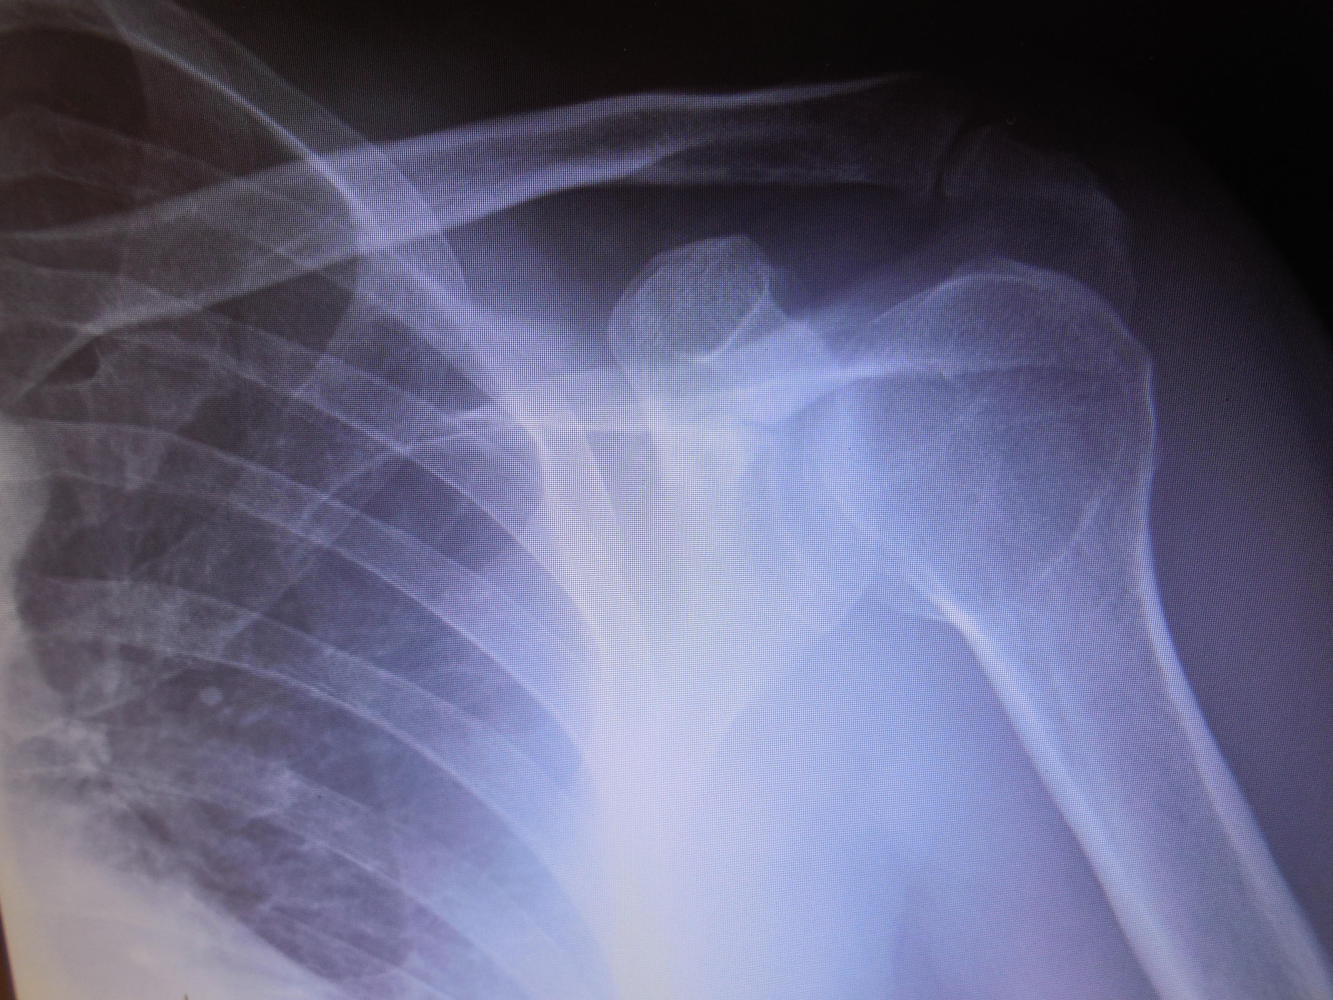

Another difference, probably just because our town is smallish, Dodie was in the booth with the tech, watching the new set of xrays come up onscreen. Then the doctor invited us behind the counter to give the analysis of what she was seeing. What she saw was that the fracture is a straight line, with no displacement, and the shoulder is back properly in its socket. Conclusion? Well tomorrow I will go see the orthopedic surgeon, but basically it's ok to start moving the joint gently.

Yup. it's a shoulder.

Anatomy lesson, with the conclusion - looks good!